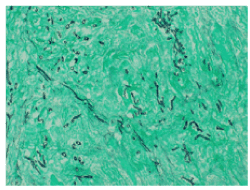

A month later, due to the progression of symptoms and an inconclusive lung function result, a new 18F-FDG PET-CT was performed and showed the above-described ametabolic kidney lesion increased in size, which now involved the whole left kidney (Figures 2A and 2B), as well as the pancreatic toe and spleen (Figure 3). A biopsy of perirenal hypermetabolic tissue, guided by PET/CT findings, was performed and histopathology showed abundant elongated structures in the form of thick, non-septate hyphae, with branches at right and obtuse angles, which with Grocott's silver stain showed thick contours (Figure 4). These findings lead to the final diagnosis of mucormycosis caused by Rhizopus oryzae. Due to involvement of such organs and the difficulty of its surgical debridement, the patient received medical treatment based on amphotericin B and Isavuconazole.

Figure 4. Histopathological images were studied using "Grocott stain", in which the microorganisms are seen as thick, elongated, cylindrical black structures and green background corresponds to necrotic perirenal fatty tissue